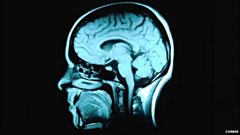

'Deep learning' technology inspired by human brain